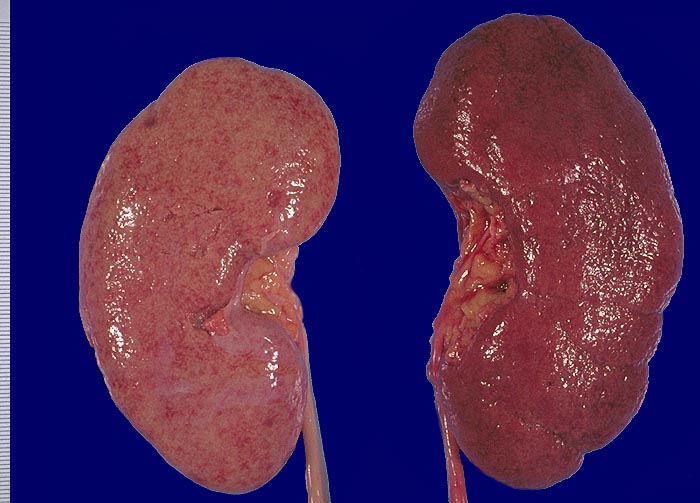

Noduläre Glomerulosklerose links, Arteriolosklerose rechts

Links: Diabetikerniere mit fein granulierter Nierenoberfläche und gelblich-roter Farbe.

Rechts: Niere bei arterieller Hypertonie stärker rot und ebenfalls fein granuliert.

Linke Niere: Diabetes mellitus Typ I. Fortgeschrittene Niereninsuffizienz.

Die diabetische Niere ist im allgemeinen vergrössert, die Oberfläche granuliert und die Konsistenz derb. Bei schwerer Atherosklerose und fortgeschrittener Niereninsuffizienz kann die Niere auch normal gross oder verkleinert sein.